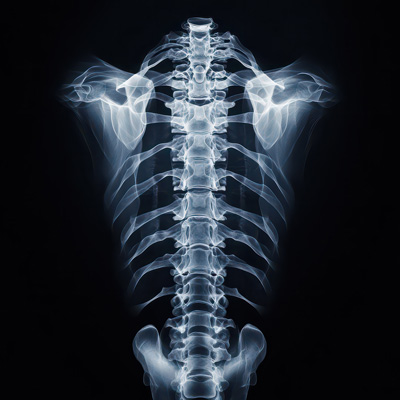

Scoliosis Newport Beach: Offering a non-surgical, safe, and effective solution to reverse your scoliosis!

If you or a loved one is suffering with scoliosis, we would love the opportunity to help. Our state-of-the-art scoliosis correction brace called ScoliBrace not only stops the progression of your scoliosis, but reverses it!